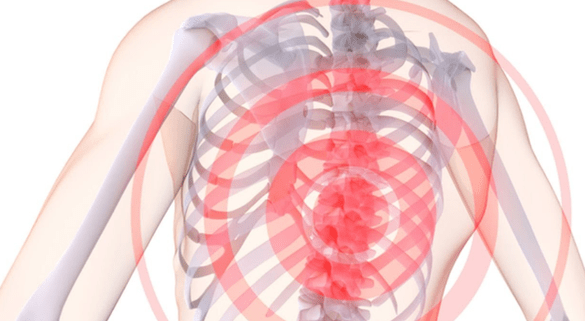

Што лічыцца абвастрэннем хваробы?Пад гэтым тэрмінам разумеюцца выяўленыя болевыя адчуванні.Калі пацыент адчуў прыкметны дыскамфорт, знаёмыя прастрэлы і тупыя болі ў вобласці грудзей, якія радыіруюць у брушыну, паясніцу і рукі, то значыць, прыйшоў час надаць максімальную ўвагу свайму захворванню.

У час абвастрэння рэкамендуецца:

- пазбягаць пераахаладжэнняў і стрэсаў;

- як мага менш знаходзіцца ў нерухомых позах, пры якіх захоўваецца нагрузка на пазваночнік;

- накладваць на хворы ўчастак зберагалыя кампрэсы і мазі, не якія валодаюць занадта рэзкім дзеяннем;

- асцярожна масажаваць хворыя ўчасткі самастойна - але пазбягаць моцнага націскання;

- па меры сіл працягваць лячэбную фізкультуру - але толькі ў тым выпадку, калі гэта не прыводзіць да ўзмацнення боляў.

Пры вострым праходжанні ўскладненні рэкамендуецца таксама пасцельны рэжым.Пры ўзнікненні нясцерпных боляў можа быць нават ажыццёўлена шпіталізацыя.Але ў большасці выпадкаў абвастрэння груднога астэахандрозу ўдаецца купіраваць у хатніх умовах, асабліва калі спалучаць зберагалы рэжым з прыёмам медыкаментаў, прызначаных спецыялістам.

Галоўнай умовай пры абвастрэнні астэахандрозу з'яўляецца адсутнасць фізічных нагрузак.Якія запаліліся міжпазваночных дыскам неабходны максімальны супакой - тады зладзіцца з абвастрэннем атрымаецца хутка.